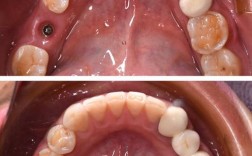

随着口腔医疗技术的进步,种植牙已成为缺牙修复的重要选择,在日本,种植牙技术发展迅速,不仅材料先进,手术方式也在不断优化,本文将介绍日本种植牙的现状、技术特点、费用以及最新数据,帮助有需求的患者更好地了解这一治疗方式。

日本种植牙的主要技术与材料

日本在种植牙领域的技术处于世界领先水平,主要采用以下技术:

- 传统种植牙需等待3-6个月骨结合,而即刻种植可在拔牙后立即植入种植体,缩短治疗周期。

- 适用于牙槽骨条件良好的患者,成功率可达95%(日本口腔インプラント学会数据)。